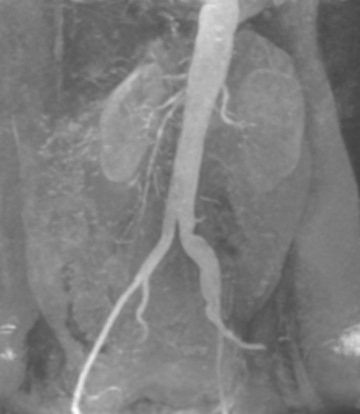

Figure 10.15(a) [6] (a) Give the main steps of edge finding using the zero-crossings of the Laplacian of Gaussian (b) Implement and apply this method to the angiogram image from Fig. 10.15(a) (as in Fig. 10.22 for the house image, but you will apply your method to the angiogram image)